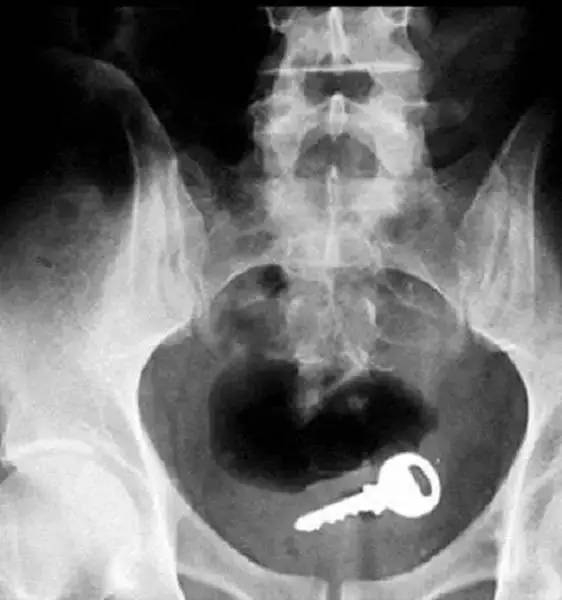

还有人吞下一把钥匙……